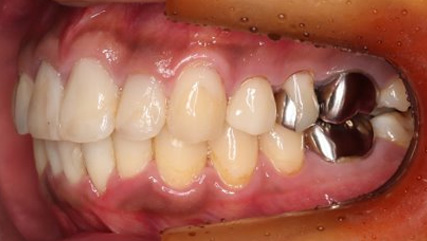

上顎前突といわれ、上顎の前歯が唇側に出ている状態を言います。

前歯が出ることで見た目の問題もありますが、口を閉じることができない、口呼吸をしてしまう、外傷などのリスクがあります。

日本人に叢生の次に多い不正咬合と言われており、自然に治ることはありません。また上の前歯が出ている事だけが気になるかもしれませんが、多くの場合、上顎の奥歯の位置に問題があることが多く、部分矯正でなく根本的な治療をした方がいい場合が殆どです。

口を閉じることができないことで、鼻呼吸でなく口呼吸をしてしまい、結果、成長期の場合顎の骨の成長を邪魔してしまうとも言われております。その他、口呼吸はアトピーなどを含むアレルギー症状の悪化、風邪を含むウイルス性の感染症にかかりやすいなどのリスクも増大してしまいます。

歯並びだけでなく全身への影響も多い為、早期の治療をおすすめ致します。